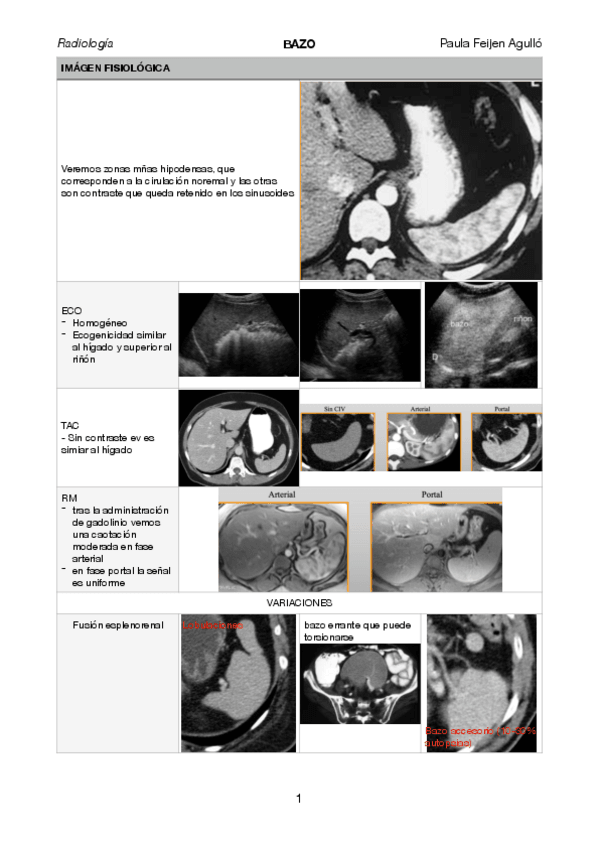

bazo.pdf